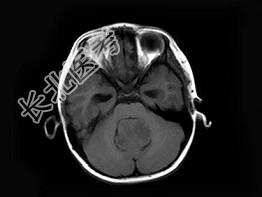

- 单项选择题女,3岁, 头痛4个月,MRI平扫及增强扫描, 最可能的诊断为 ( )

A、第四脑室脑膜瘤

B、第四脑室室管膜瘤

C、第四脑室乳头状瘤

D、第四脑室星形细胞瘤